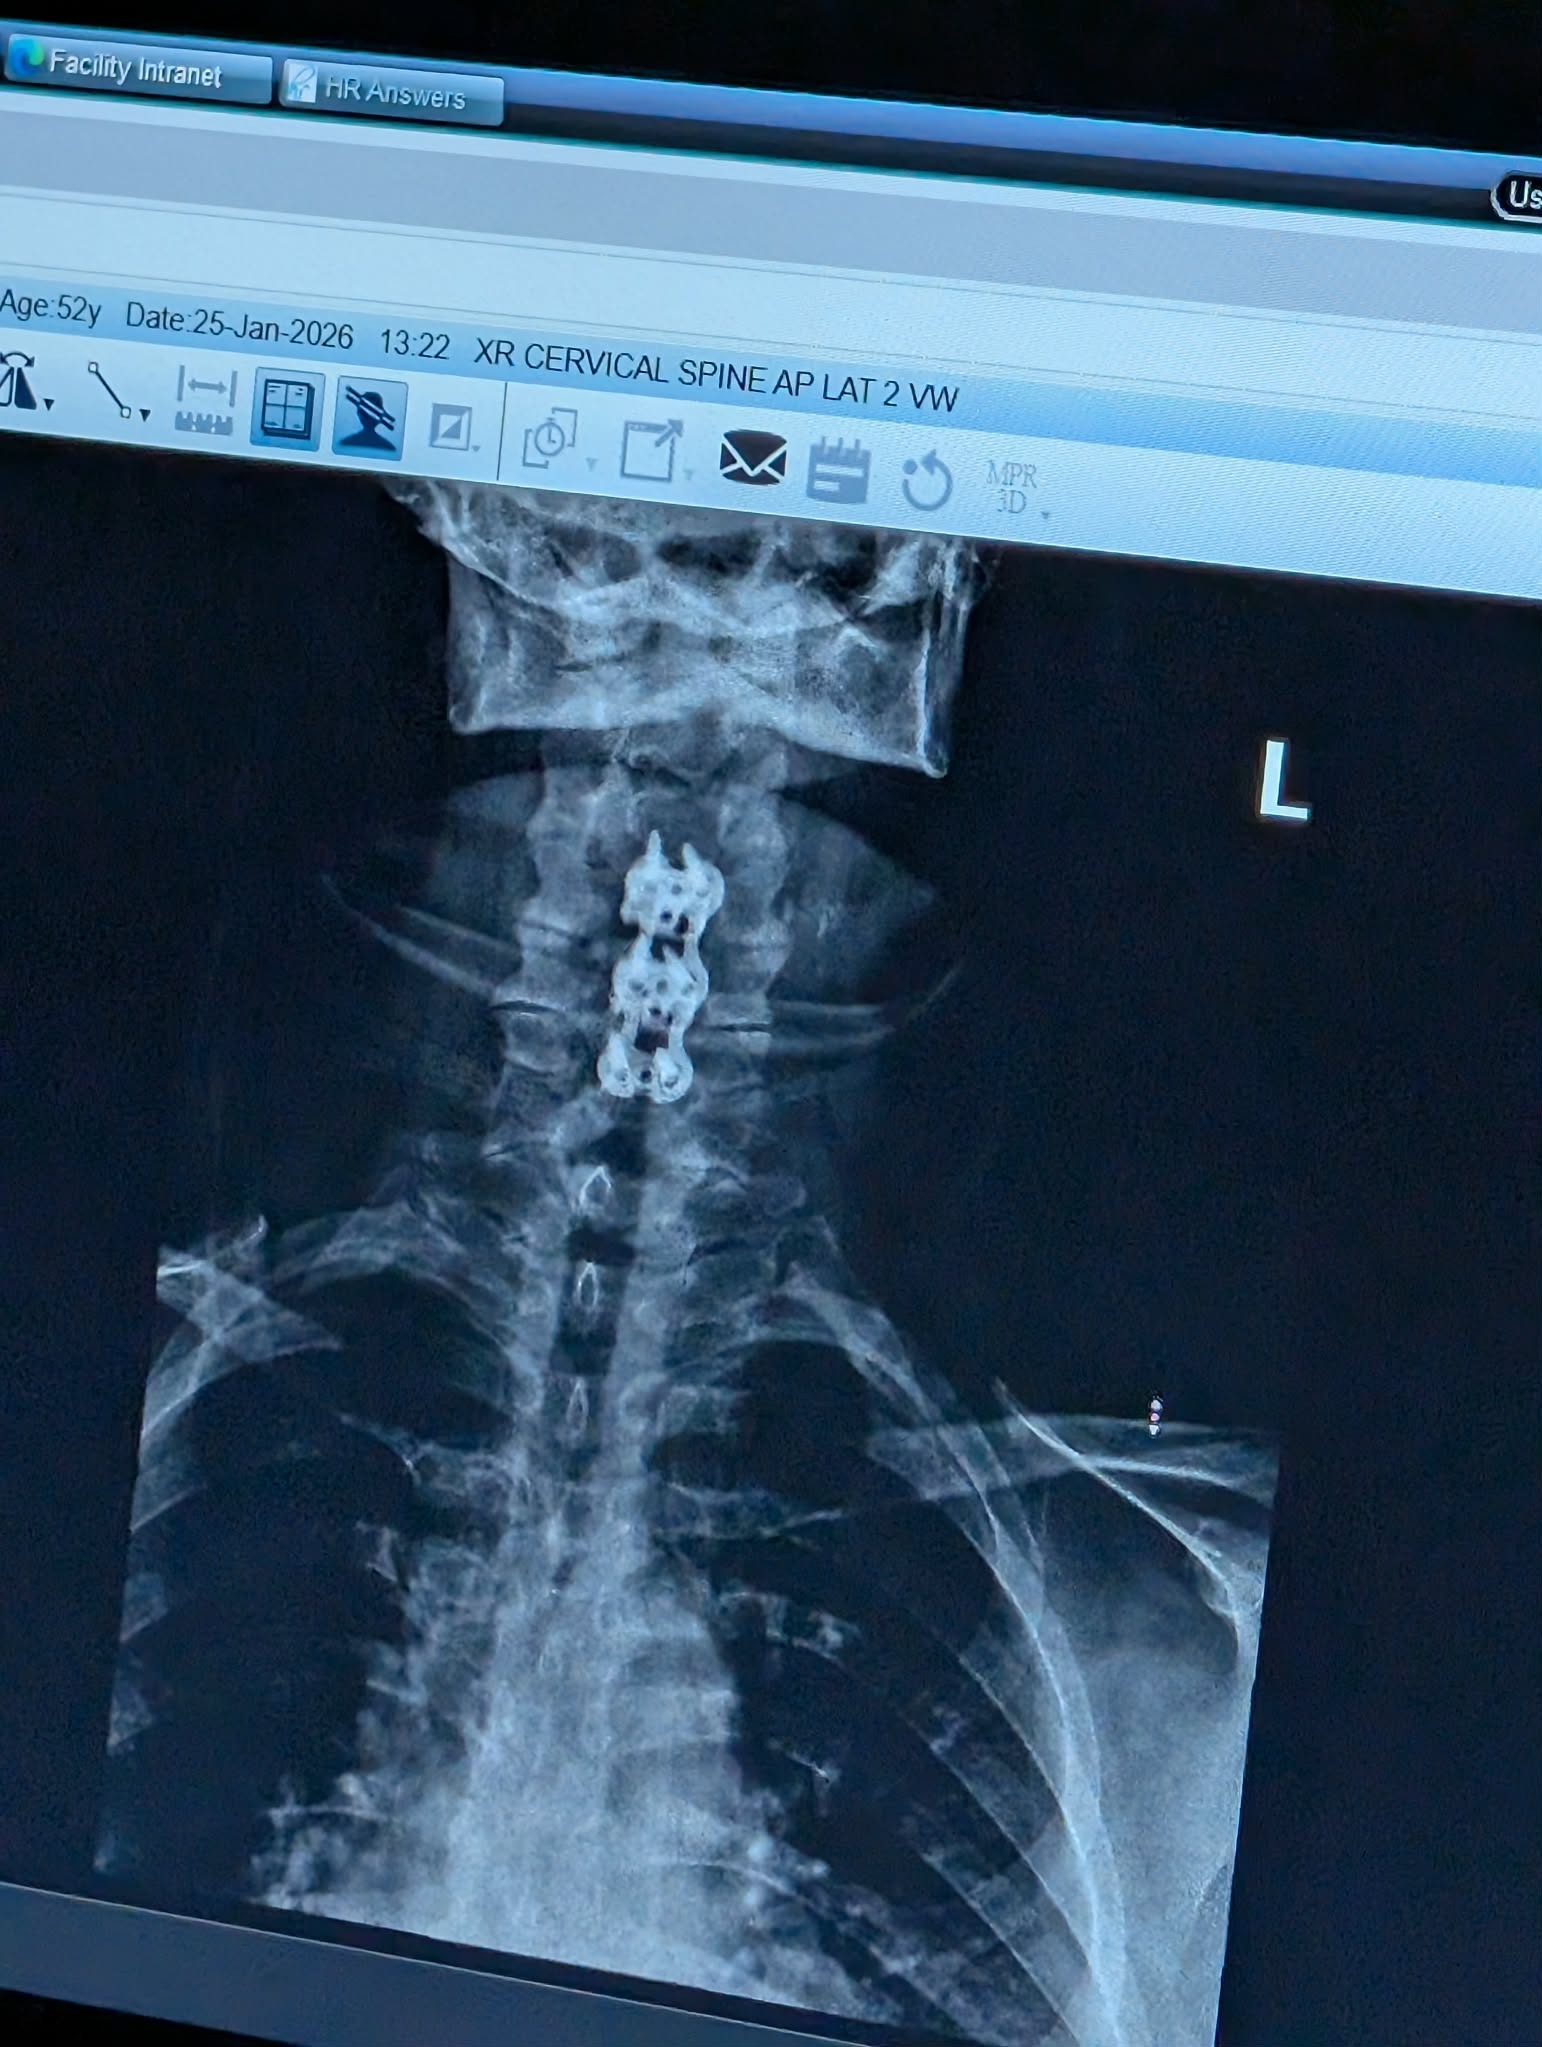

My sister Mona suffered a terrible fall early morning on January 22nd, breaking her neck and requiring emergency surgery that evening. The herniated discs pressed down on her spinal cord, causing severe nerve damage. As of now, Mona is considered a total care quadriplegic. My family and I are anticipating her release from the hospital on February 19th, and we are doing everything we can to prepare for her return home.